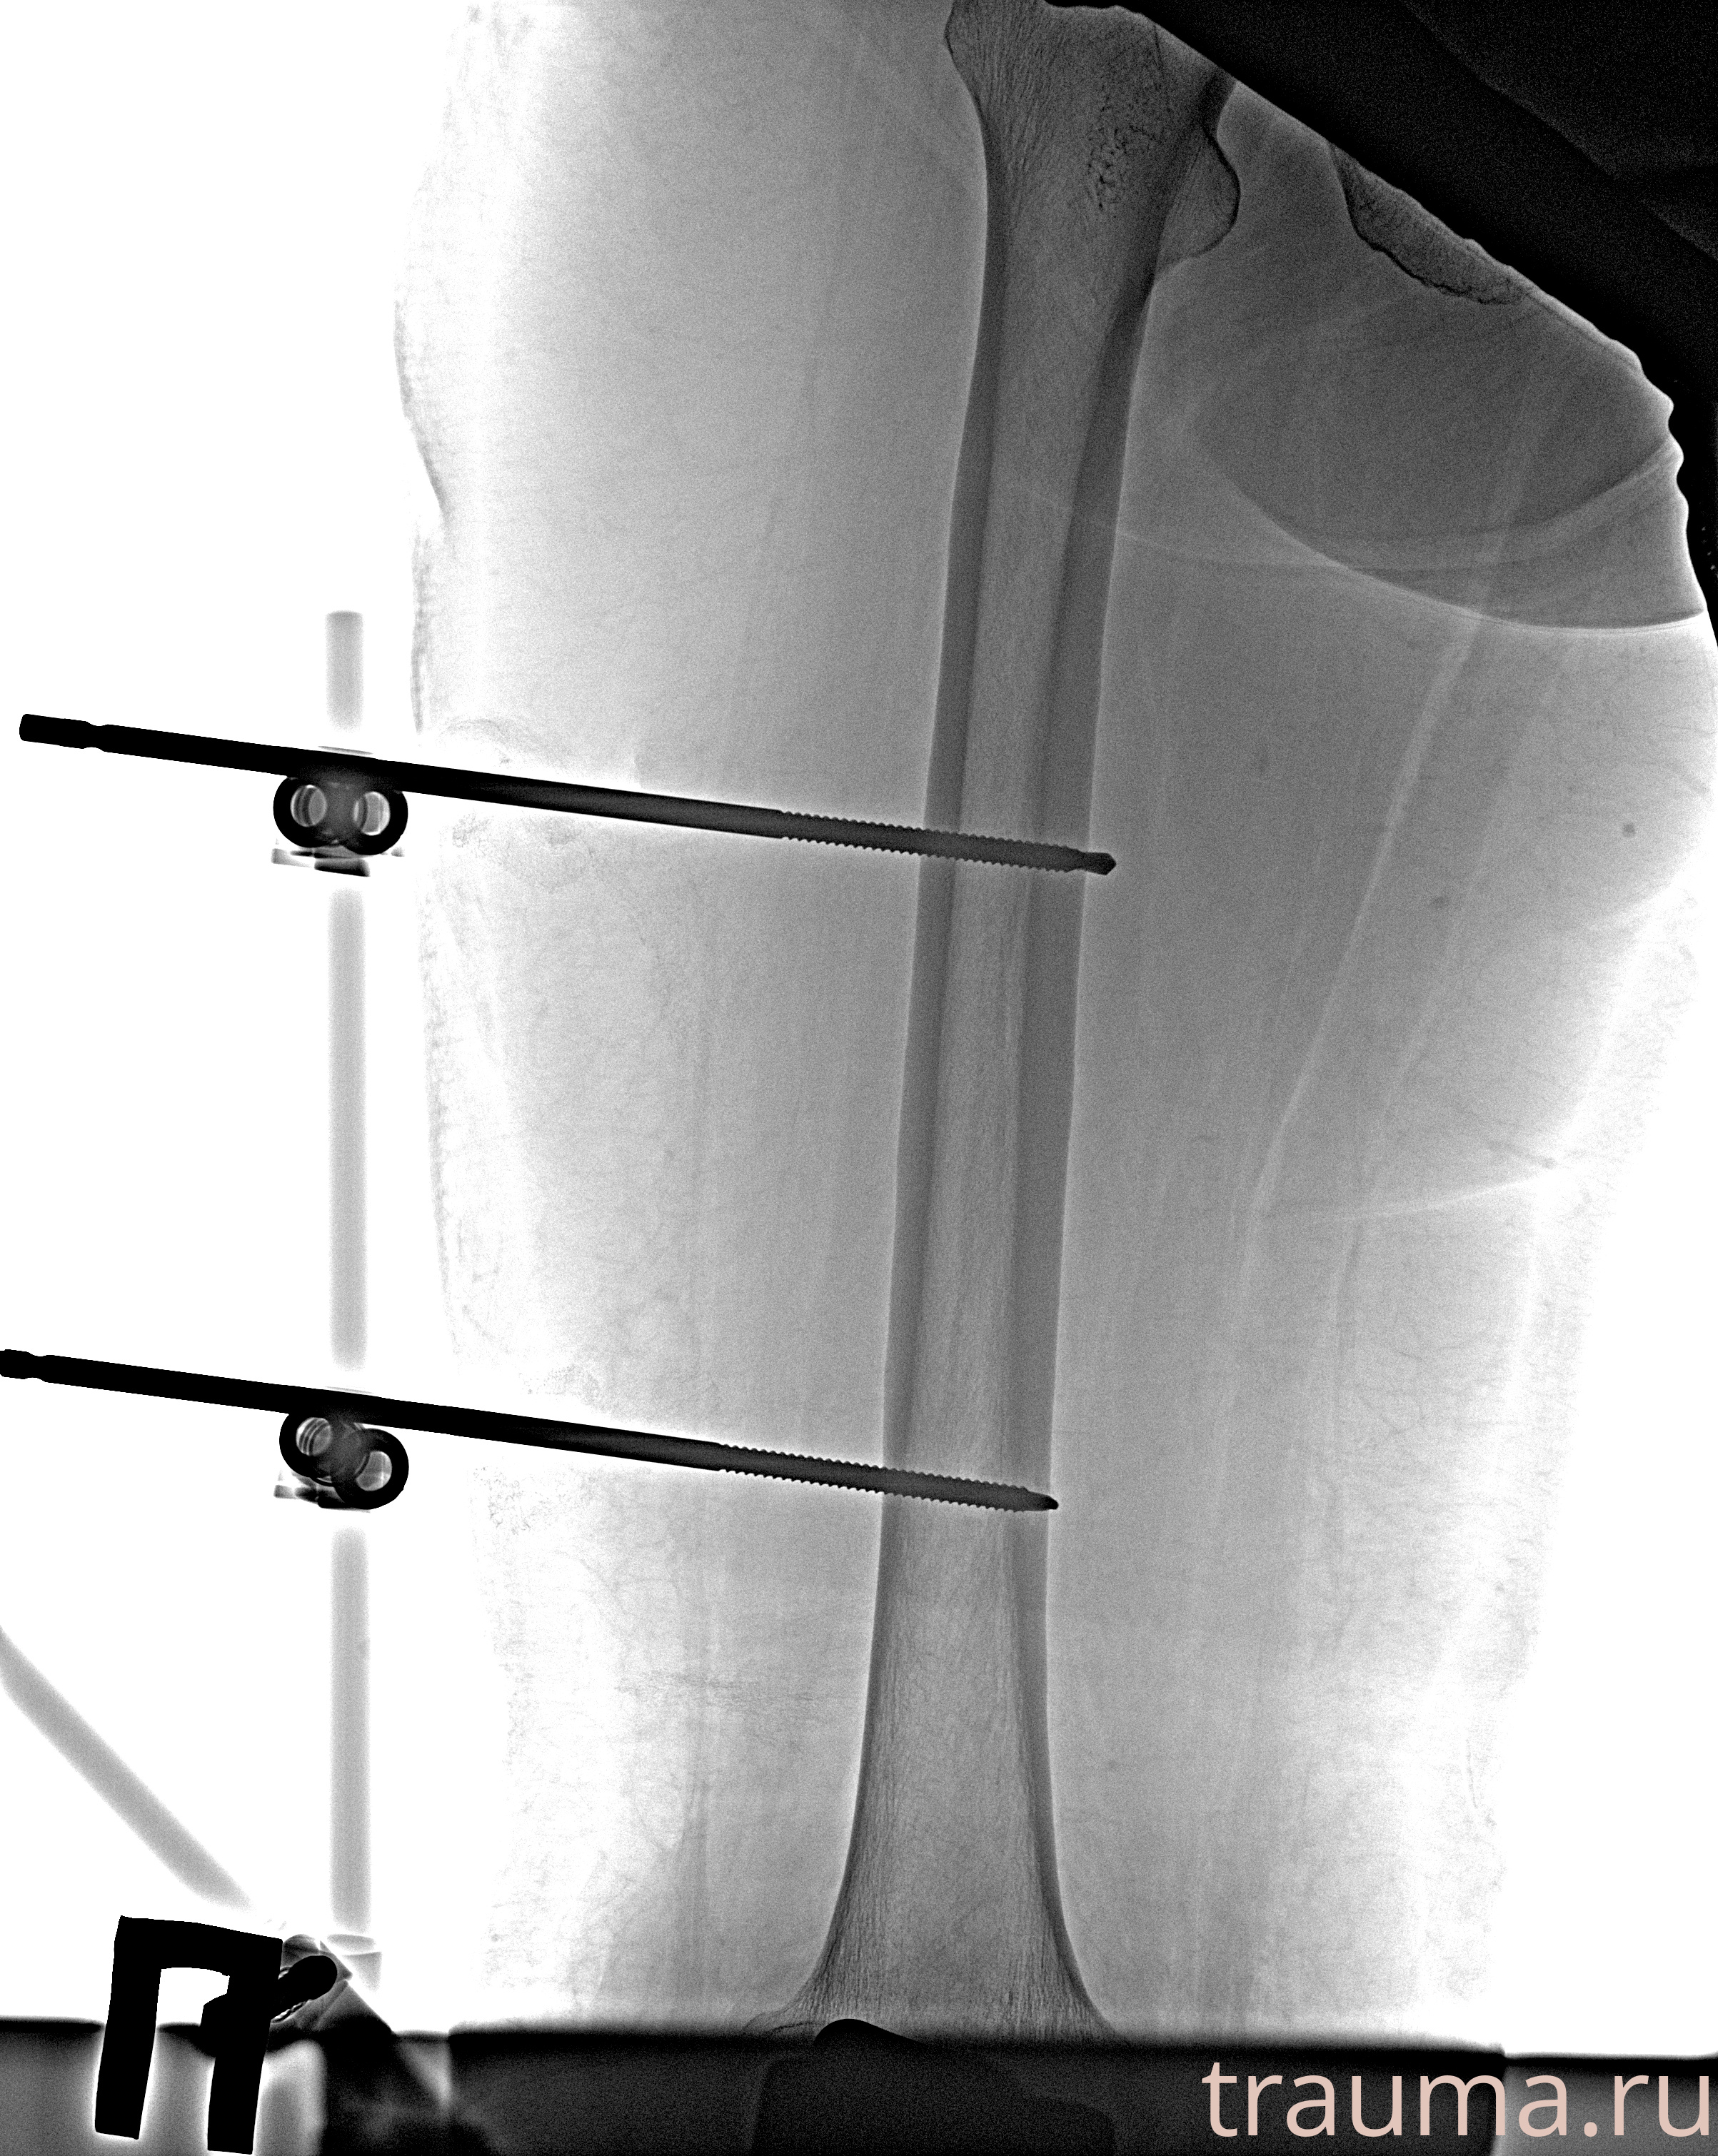

Рентгенограммы

Рентген на дому: по вашему адресу приезжает врач-рентгенолог, травматолог-ортопед с мобильным рентгеновским аппаратом, проводит диагностику травмы или заболевания, делает необходимые рентгенограммы, дает рекомендации по дальнейшему лечению. Получить качественные снимки в домашних условиях возможно благодаря уникальной методике, разработанной МосРентген Центром для института  Склифосовского

Видео КТ после вправления и наложения АНФ